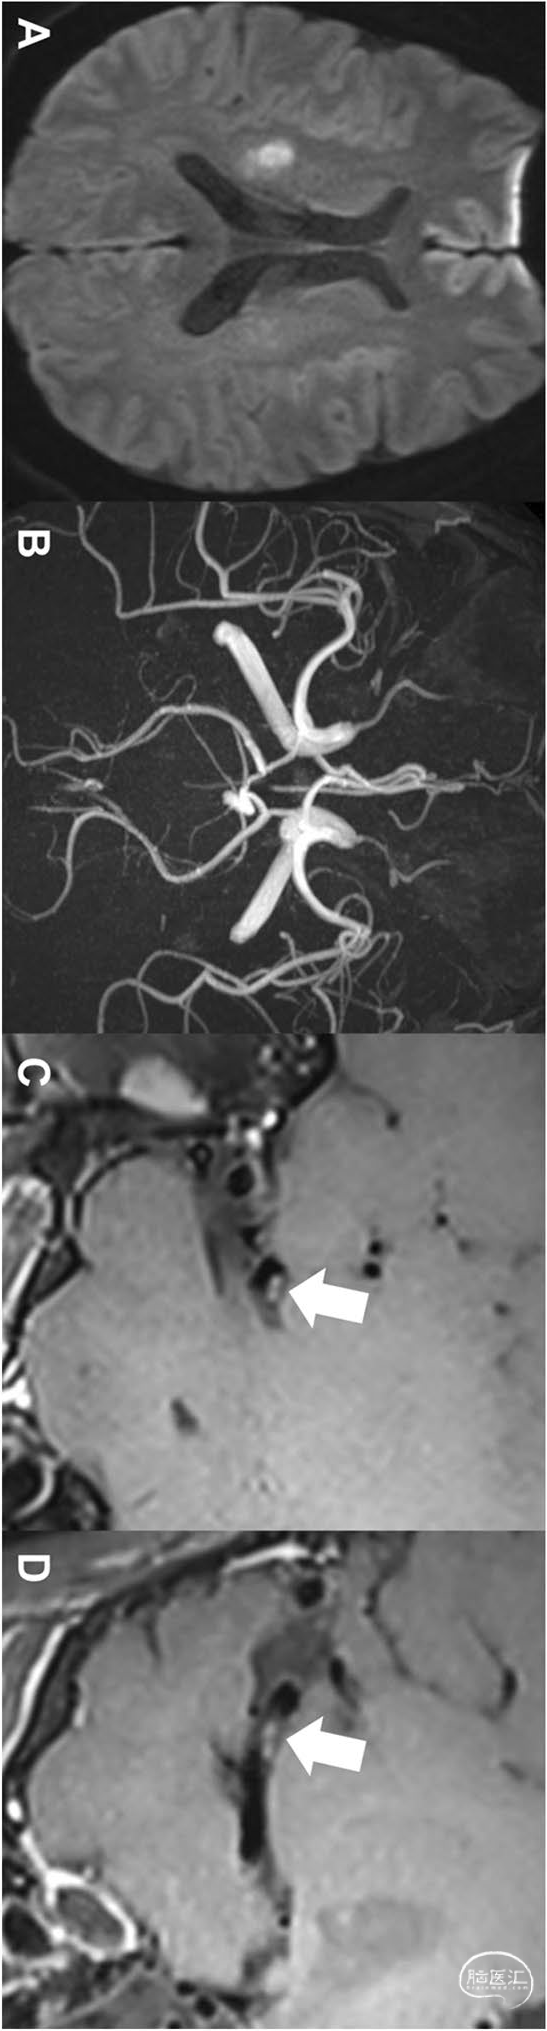

男性,36岁,表现为四肢无力和麻木。除了低密度脂蛋白胆固醇水平略有升高外,没有发现任何传统的危险因素。心电图和经颅超声心动图均未发现异常。DWI显示右侧皮质下单个梗死(a)。MRA未见明显狭窄血管狭窄(B)。根据传统检查结果,该患者病因分类为小动脉闭塞性中风。然而,增强HRVWI(C,D)显示大脑中动脉上壁斑块(罪犯病变)(白色箭头)。加上HRVWI后,卒中病因改变为大动脉动脉粥样硬化: